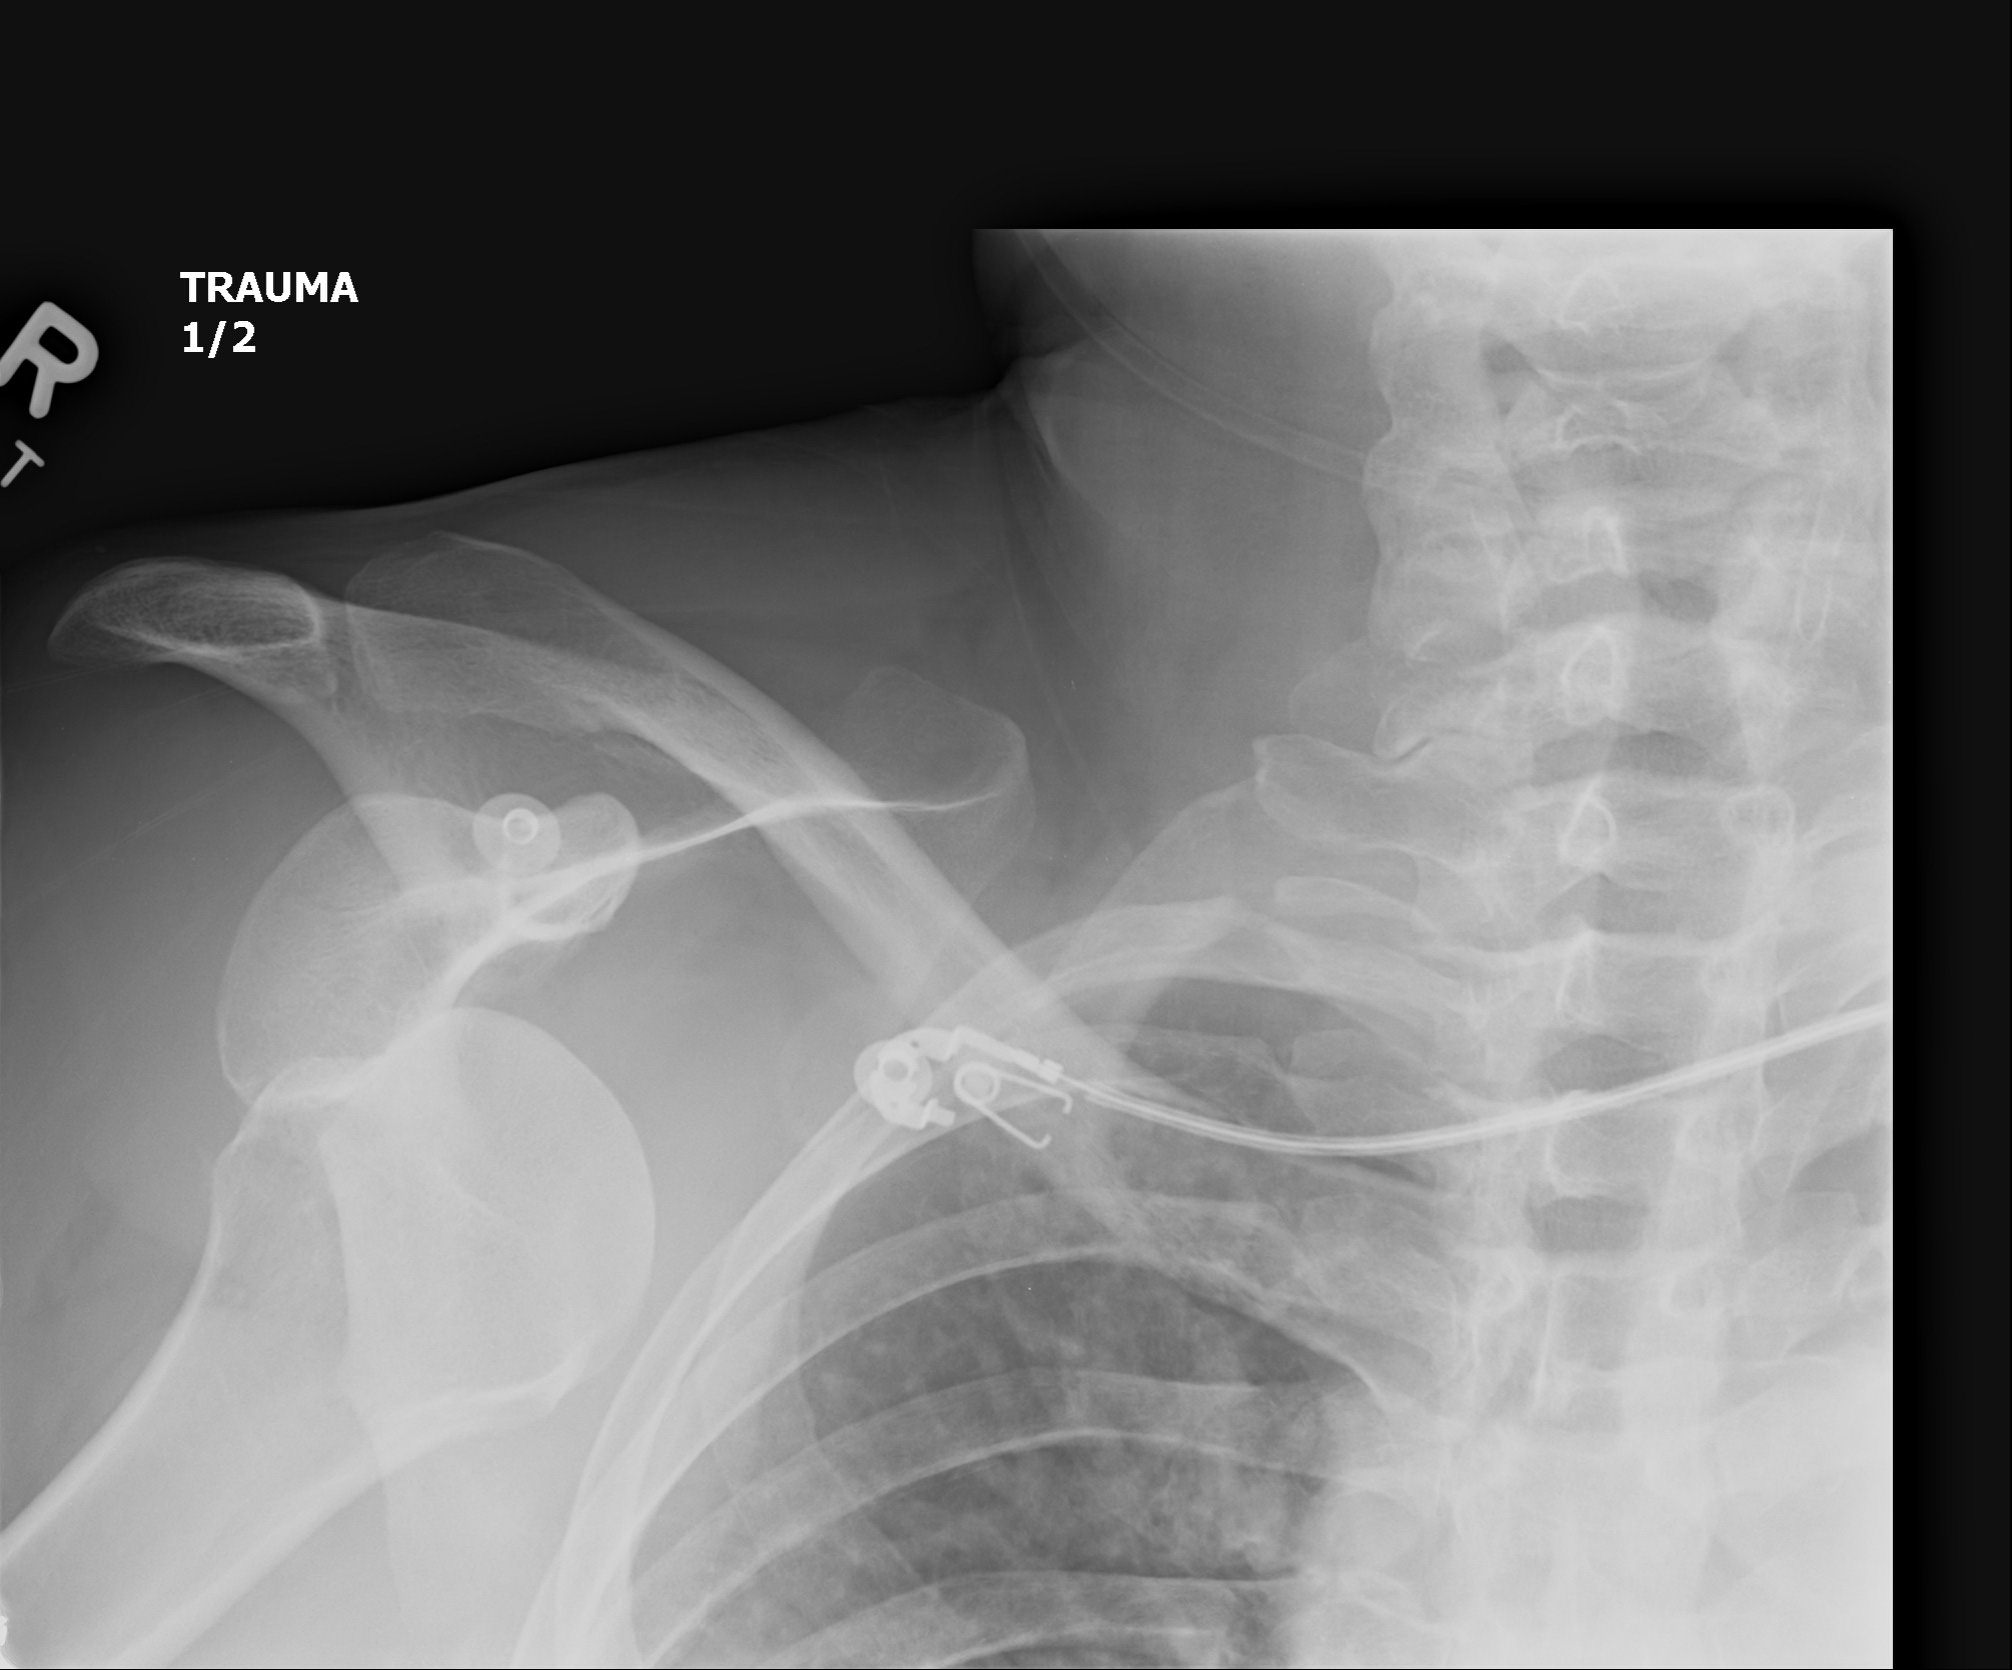

Nonetheless, as welfare science likes to term it, it’s entirely “a life worth living”. I have to pick my battles more than I used to, and I’ve had to learn to take more time to get exercise, rest, and avoid the stresses (or even unpleasant people) that can cause my health to take rapid downward spirals. I’m more fragile in many ways, such as having to stop doing karate because my shoulders have weakened. Here’s some interesting anatomy for you from a recent MRI scan of my right shoulder:

My left shoulder in top cross-sectional view, with the missing parts of my humeral head crudely outlined in red. There's more amiss here, too.

My left shoulder in top cross-sectional view, with the missing parts of my humeral head crudely outlined in red. There’s more amiss here, too.

My seizures cause my shoulder flexors to spasm, raising my arms up and crushing my humerus against my glenoid cavity of my scapula and causing occasional dislocations that abrade the humerus against the rim of the glenoid. The result, after numerous seizures, has been the wearing away of the articular cartilage of my shoulder and then the crumbling of the bony head of my humerus. Thus, once my NHS surgeon is ready to in coming months, I am due to have my coracoid process of my scapula cut off and moved, with its attached muscles and ligaments, to be screwed into the front of my glenoid cavity, bracing my humeral head more tightly against the glenoid and thereby resisting future dislocations. Luckily that operation can be done with several small incisions and endoscopy; invasive as the surgery is; thus recovery time won’t be so long.

Latarjet surgery (view of right shoulder joint [glenoid] from front): coracoid process moved posteroventrally. More details (w/videos) here.

It amuses me that all of this intense surgery looming on the horizon doesn’t worry me. I just want it done. I’ve been through a comparable surgery with my left shoulder, involving screwing my greater tuberosity back onto my humerus, so I know what recovery is like, and now that shoulder is doing fine. All that aside, my physical integrity has declined and I feel it every day. I may never return to my karate classes and earn that black belt I was seeking as a life-goal, but time will tell. I am trying to do what I can to remain as strong as I can for as long as I can.